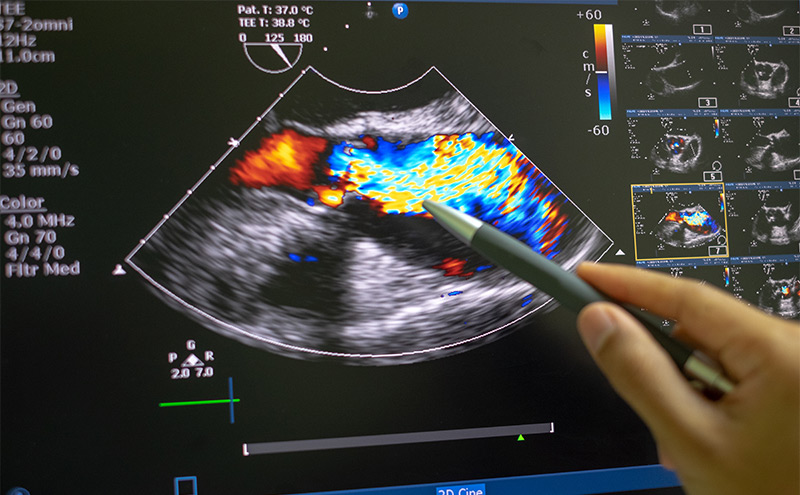

Advanced ultrasound can enhance the diagnosis of organ injury, viable tumor, and vascular pathologies at bedside.

Rapid Ultrasound for Shock and Hypotension (RUSH)